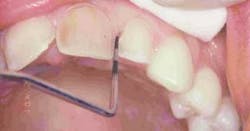

The key to successful shade-matching and duplication lies in following a standardized process and utilizing the advanced technology available, including shade-taking devices and digital photography. The Shofu Shade Eye-NCC (Figure 4) is a highly accurate, electronic shade-taking device that deduces the base shade of the tooth to be measured and provides a printout with information of that shade, value, and hue. It can be used with any porcelain system, but actually prints out an exact porcelain recipe for use with the Shofu Vintage Halo porcelain. By communicating this information to the laboratory for duplication, you can create accurate, realistic restorations that are indiscernible from its natural adjacent dentition. This is practically foolproof when you accompany the recipe with a digital photograph that captures the appropriate shade tab next to the teeth to be matched, showing any defining characteristics (such as translucency) that will make the restorations blend in as they match the texture and contour of the unprepped teeth. In this case, we measured the base shade of the untreated maxillary cuspids, and instructed the laboratory to go a half-shade lighter for the final restorations.

null